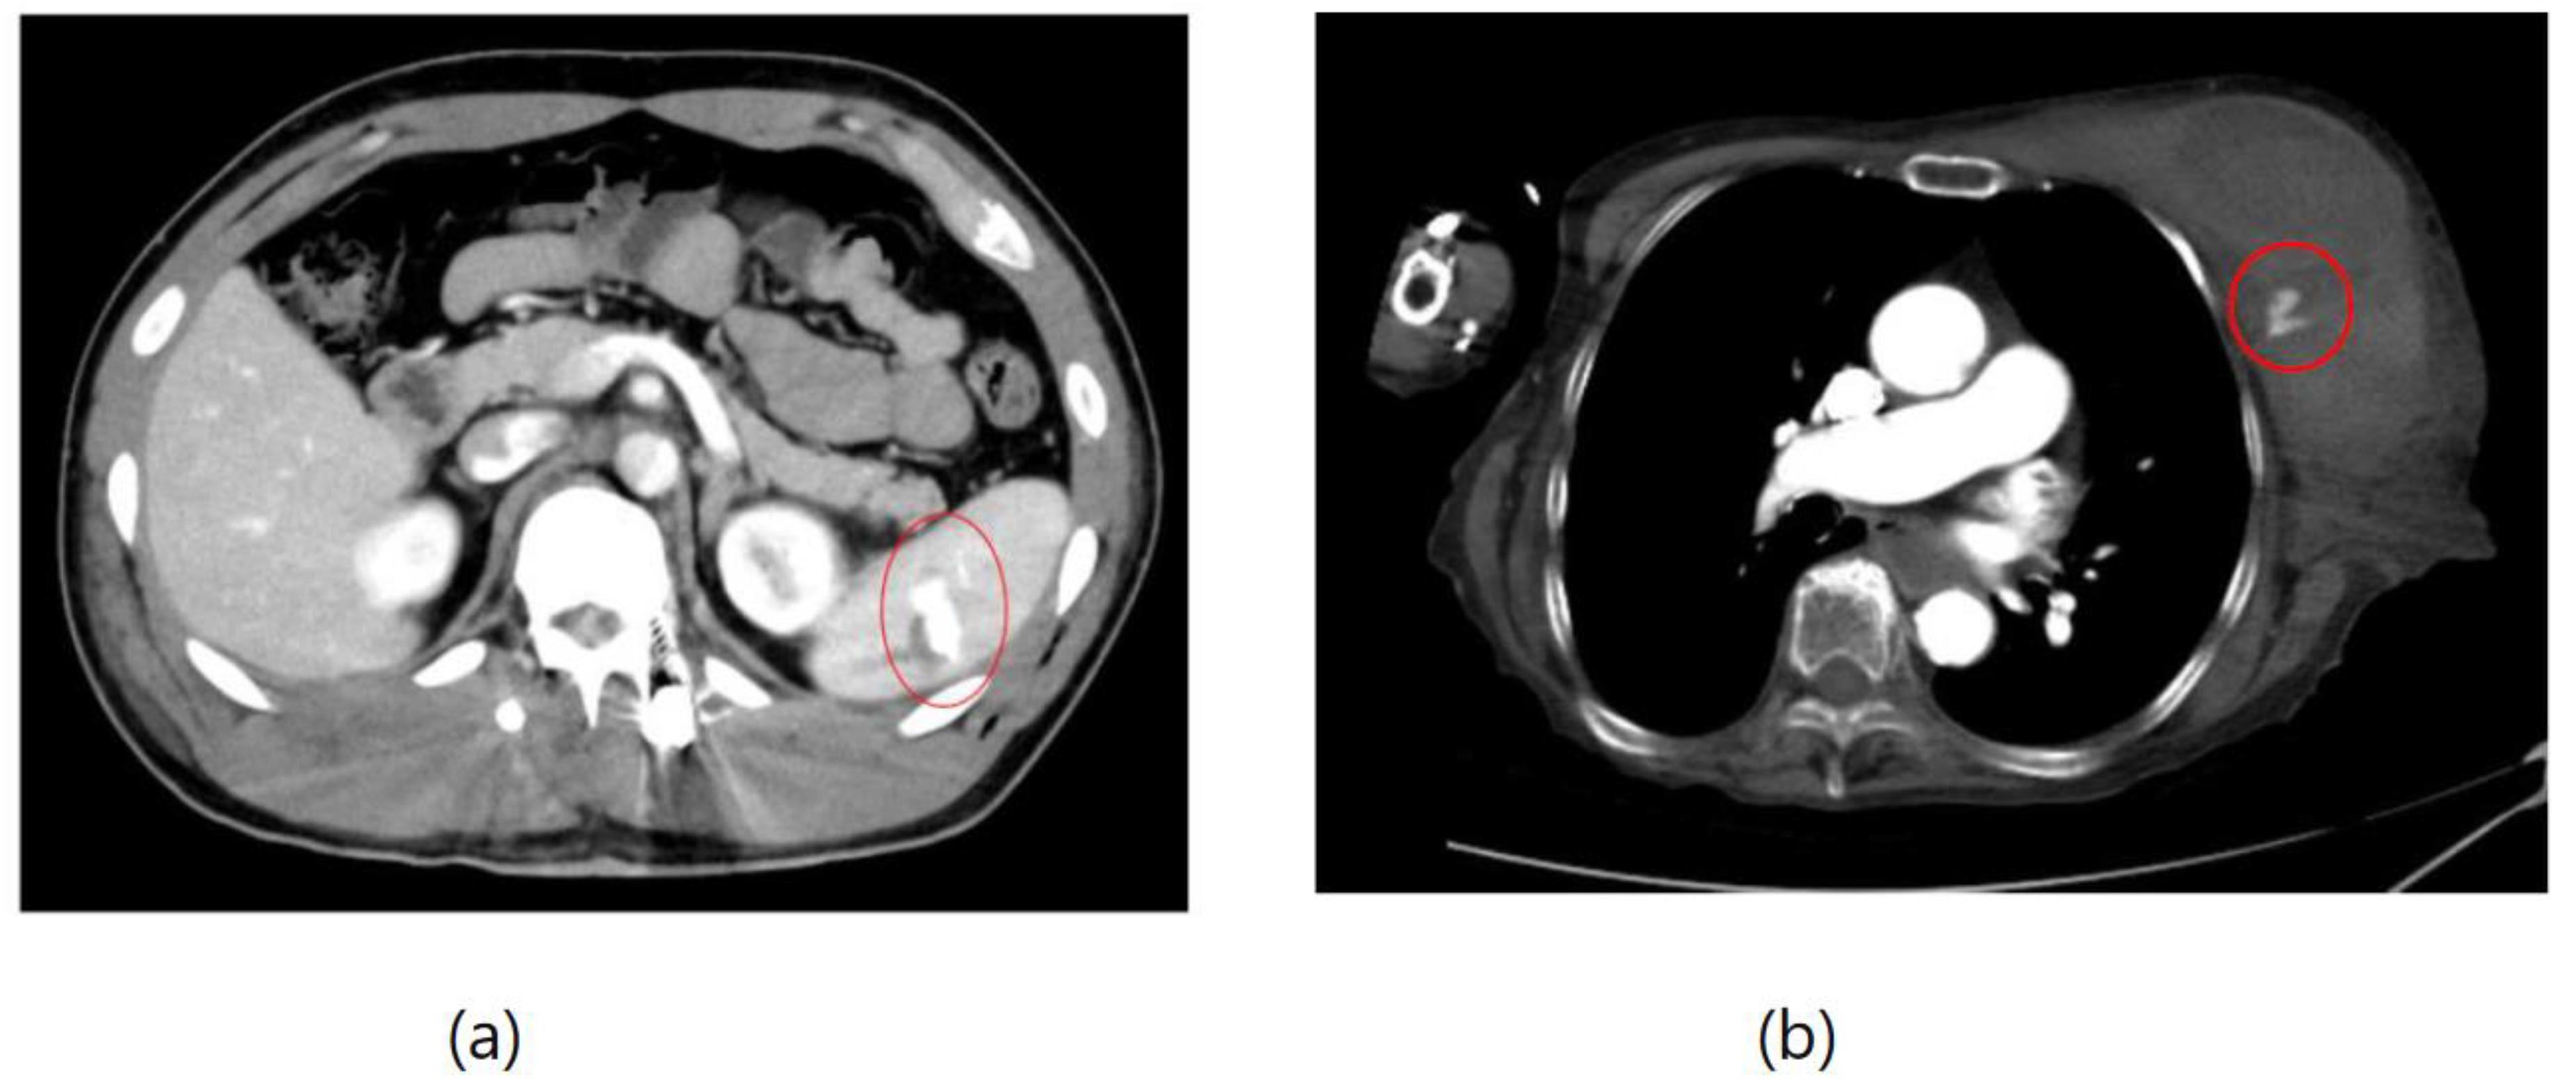

As an example, Figure 1 shows extravasation, or bleeding, from a polycystic kidney. Identifying the precise bleeding site on the computed tomography (CT) image presented a challenge. However, upon reviewing the angiography findings, it became evident that the bleeding originated from the area depicted in the CT image. In Figure 2, two instances of extravasation are depicted marked with the circles. Firstly, (a) displays a pseudoaneurysm visible post-spleen injury. Secondly, (b) illustrates a muscle hematoma in the chest region. In Figure 3, two cases of extravasation are evident. In (a), circles mark extravasation on a fractured pelvic region, indicating a significant injury. Meanwhile, (b) showcases an intragluteal hematoma, highlighting the varied presentations of extravasation across different anatomical contexts. These CT images provide valuable insights into the varied presentations of extravasation across different anatomical contexts.